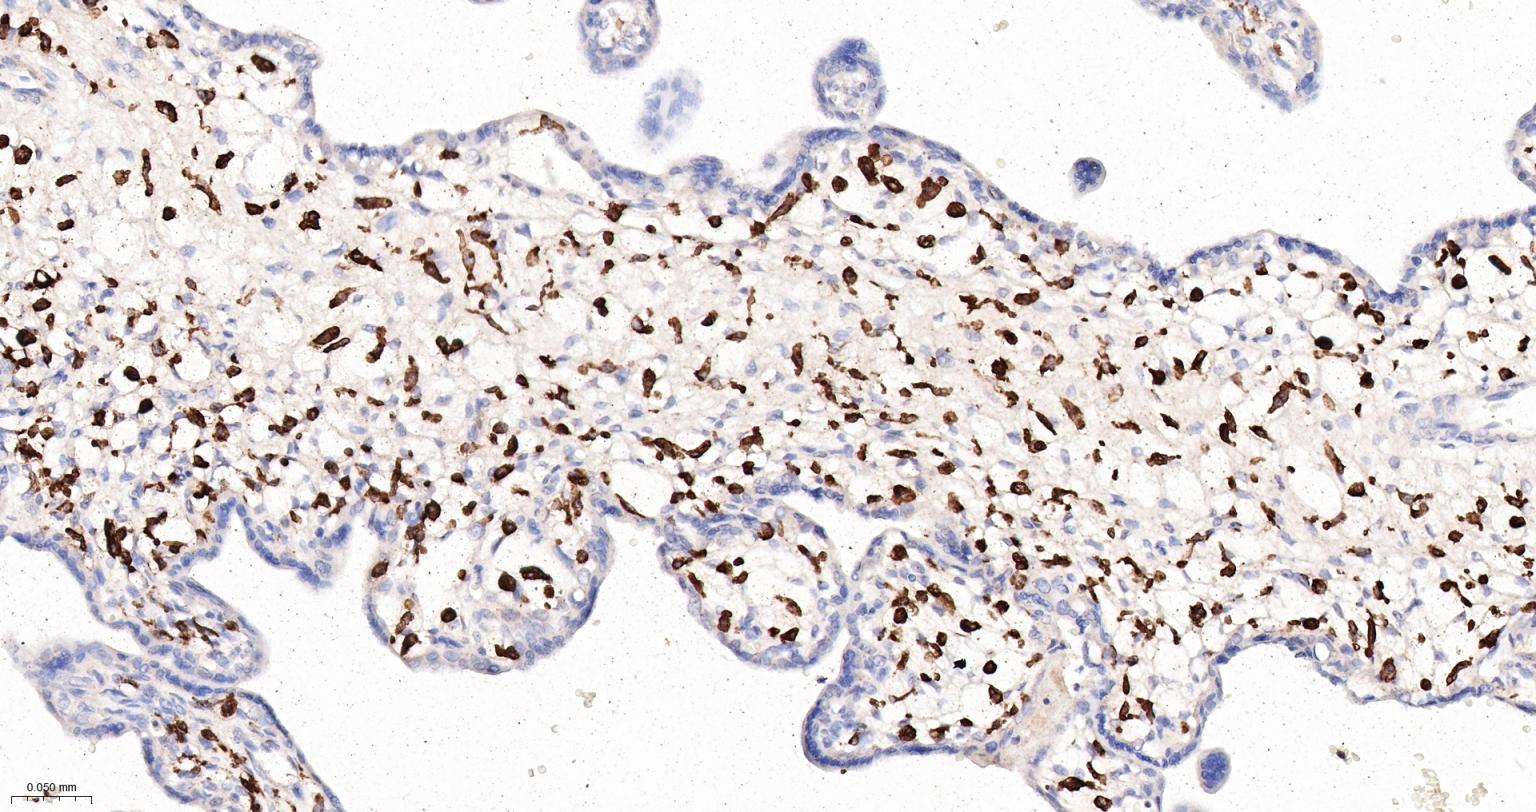

Paraformaldehyde-fixed, paraffin embedded Human Placenta; Antigen retrieval by boiling in sodium citrate buffer (pH6.0) for 15 min; Antibody incubation with CD163 Monoclonal Antibody, Unconjugated(bsm-54015R) at 1:200 overnight at 4°C, followed by conjugation to the bs-0295G-HRP and DAB (C-0010) staining.